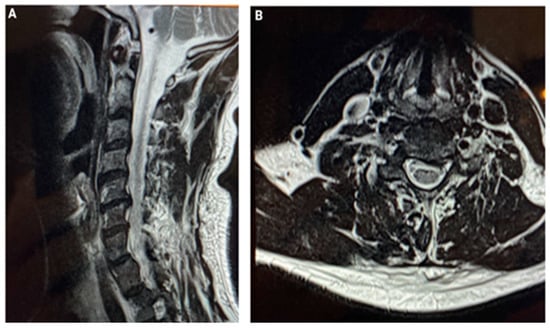

3. CASE 2: Cervical Spine Degenerative Disease